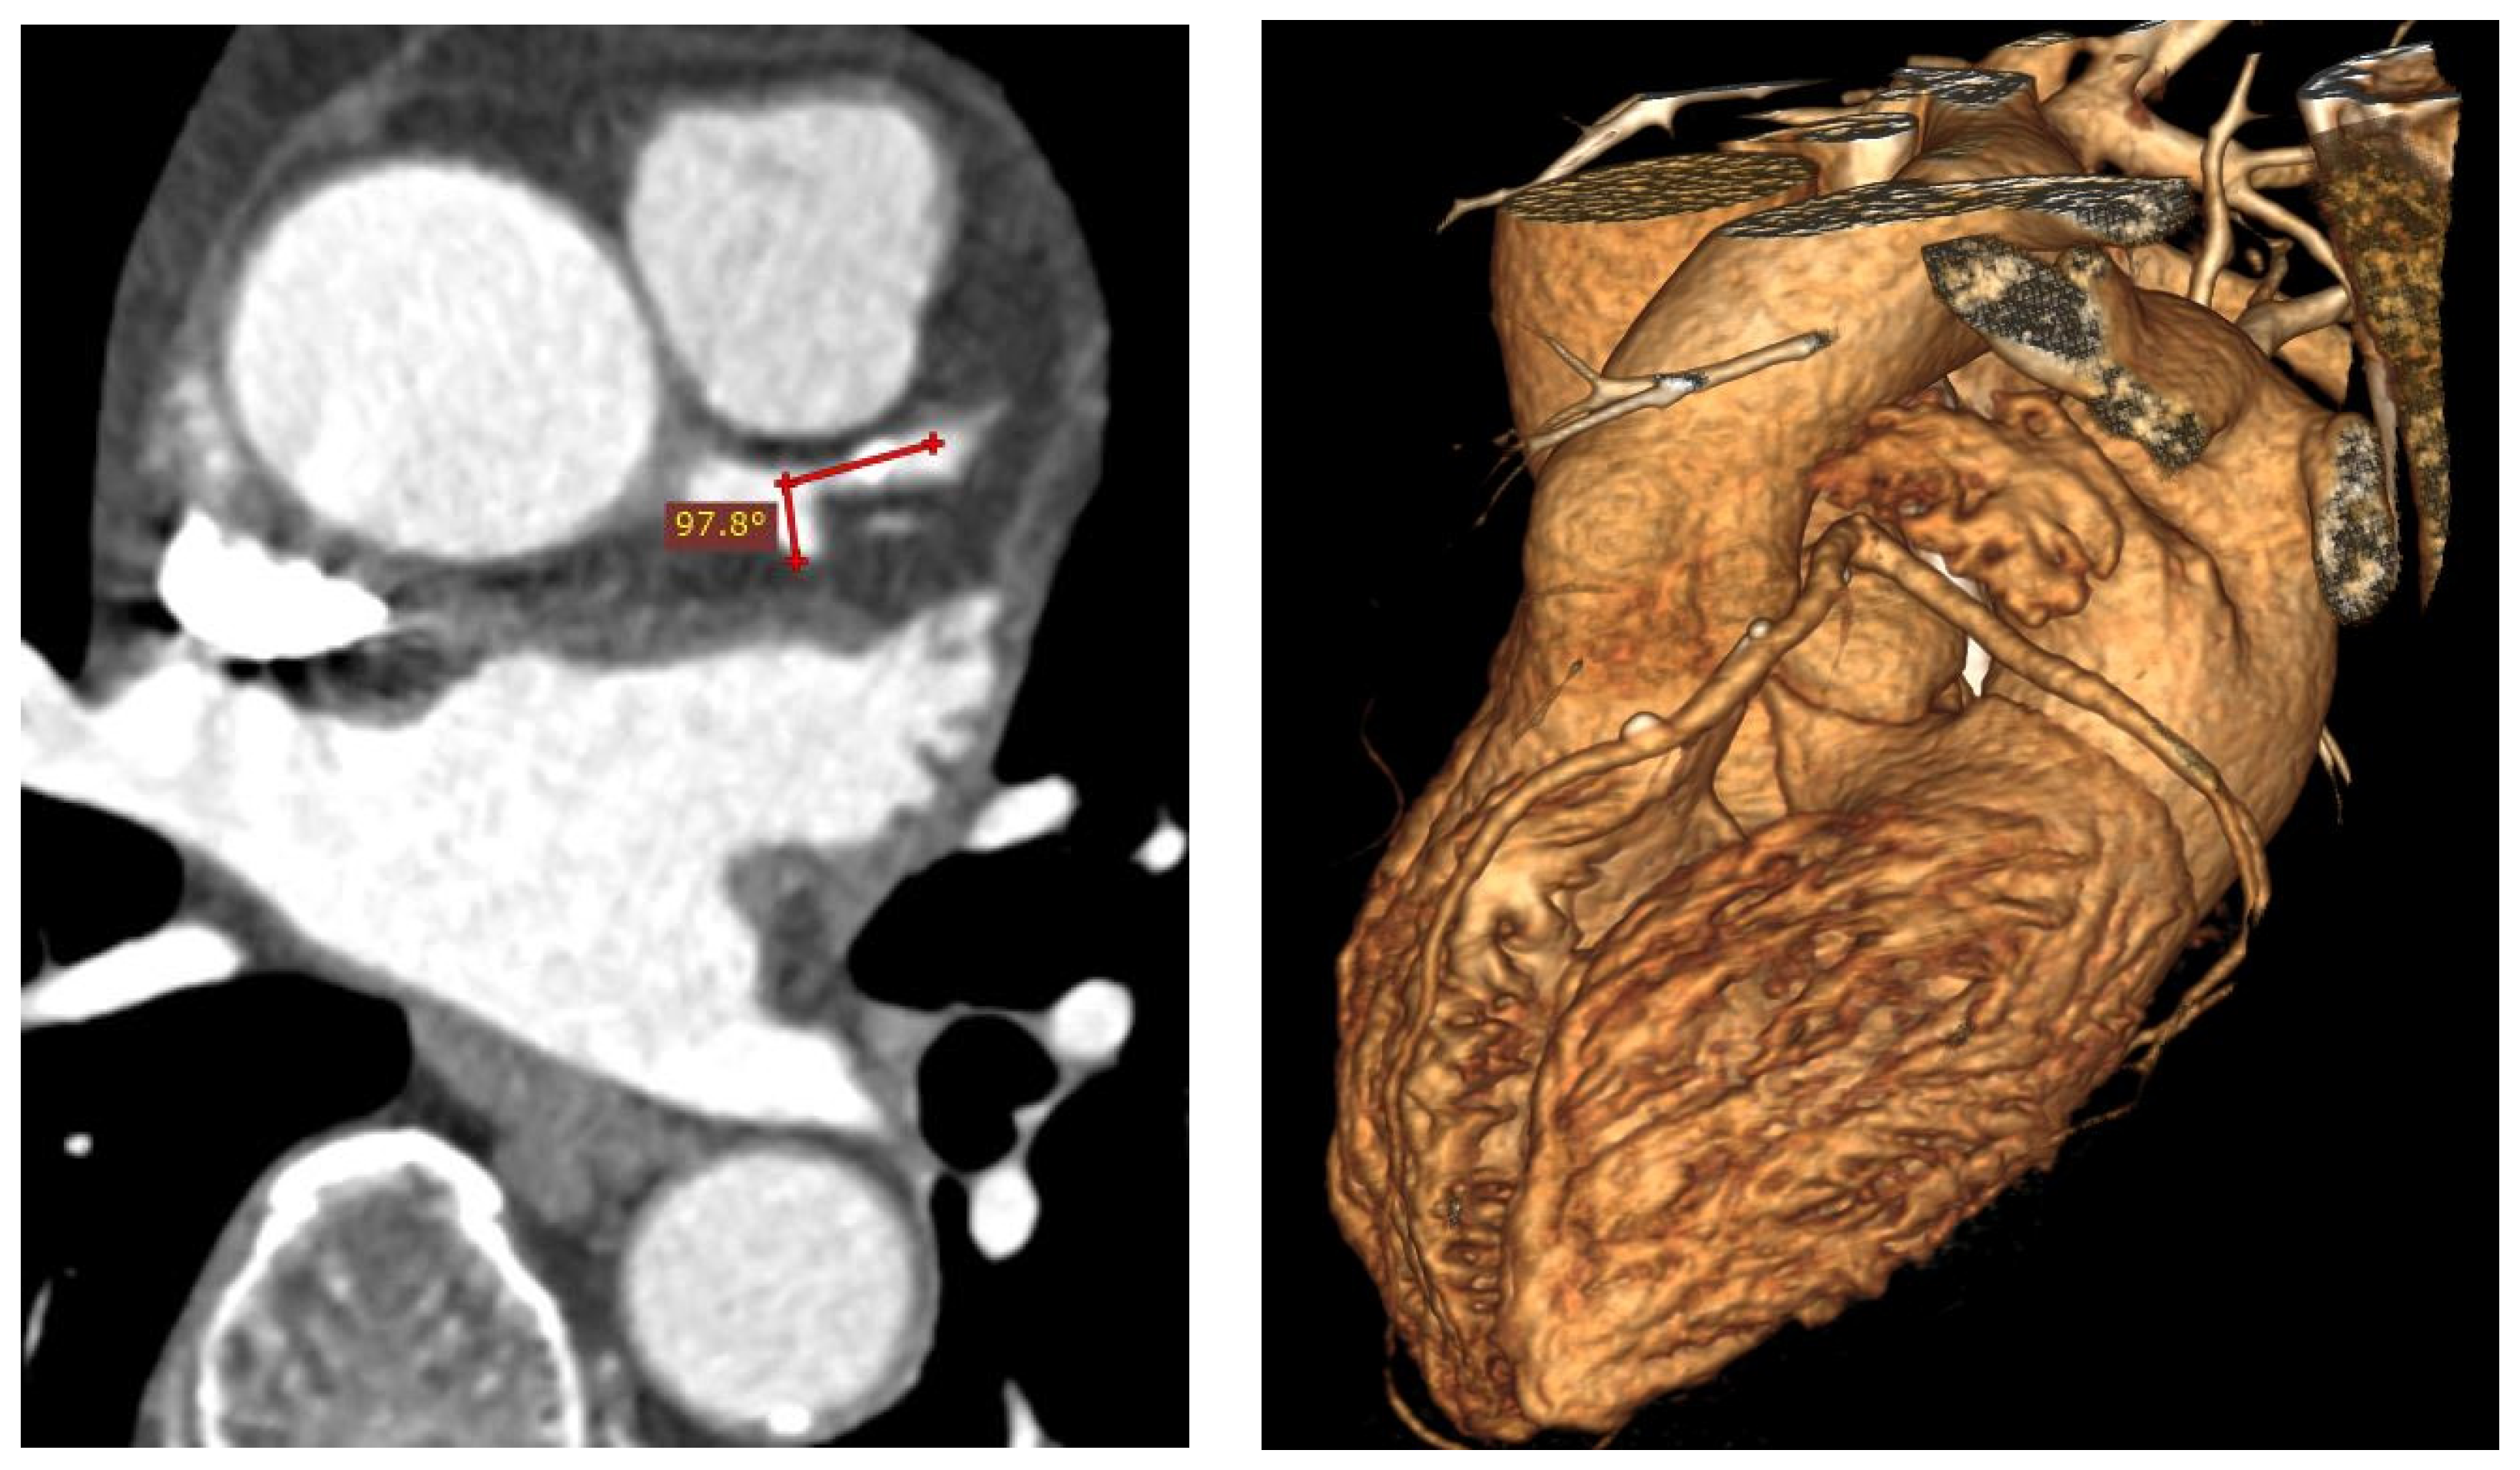

- Temov, K.; Sun, Z. Coronary computed tomography angiography investigation of the association between left main coronary artery bifurcation angle and risk factors of coronary artery disease. Int. J. Cardiovasc. Imaging 2016, 32, S129–S137. [Google Scholar] [CrossRef] [PubMed]

- Sun, Z.; Cao, Y. Multislice CT angiography assessment of left coronary artery: Correlation between bifurcation angle and dimensions and development of coronary artery disease. Eur. J. Radiol. 2011, 79, e90–e95. [Google Scholar] [CrossRef]

- Juan, Y.; Tsay, P.; Shen, W.; Yeh, C.; Wen, M.; Wan, Y. Comparison of the left main coronary bifurcating angle among patients with normal, non-significantly and significantly stenosed left coronary arteries. Sci. Rep. 2017, 7, 1515–1518. [Google Scholar] [CrossRef] [PubMed]

- Cui, Y.; Zeng, W.; Yu, J.; Lu, J.; Hu, Y.; Diao, N.; Liang, B.; Han, P.; Shi, H. Quantification of left coronary bifurcation angles and plaques by coronary computed tomography angiography for prediction of significant coronary stenosis: A preliminary study with dual-source CT. PLoS ONE 2017, 12, e0174352. [Google Scholar] [CrossRef]

- Sun, Z.; Chaichana, T. An investigation of correlation between left coronary bifurcation angle and hemodynamic changes in coronary stenosis by coronary computed tomography angiography-derived computational fluid dynamics. Quant. Imaging Med. Surg. 2017, 7, 537–548. [Google Scholar] [CrossRef]